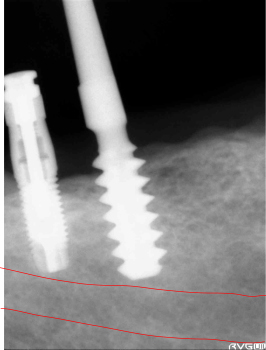

エミネオの本体を挿入します。下歯槽管までの安全性を確認します。まだ余裕があるいのが確認出来ます。 | ||